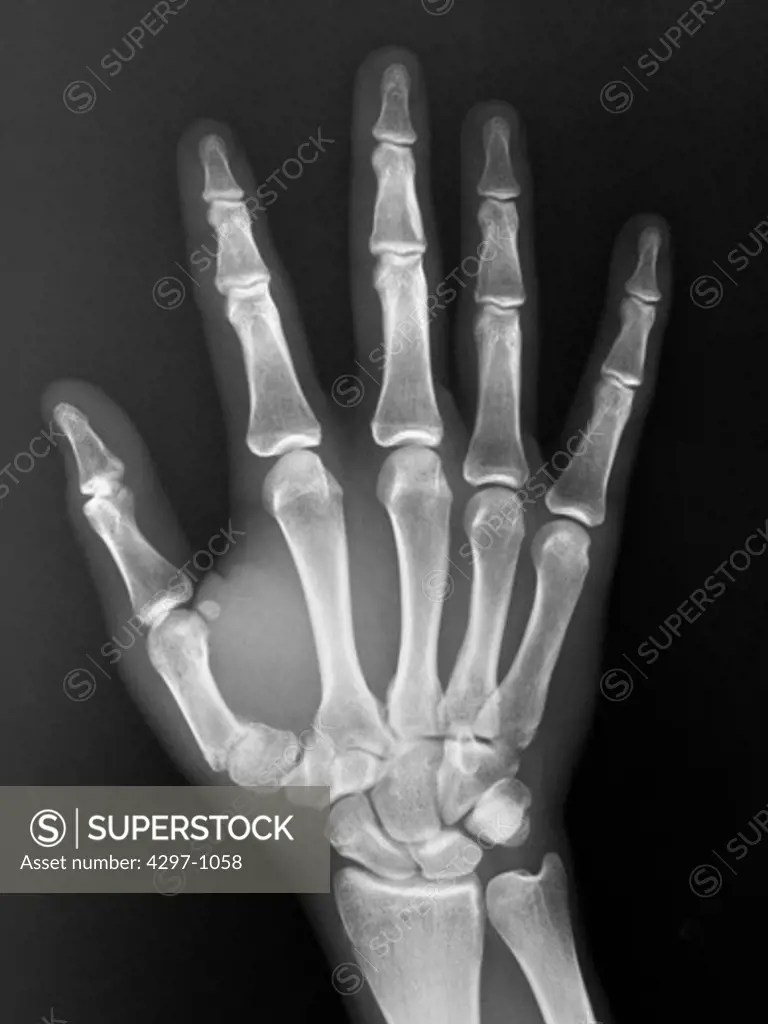

From www.superstock.com

Normal hand xray of a 19 year old boy SuperStock Hand X Ray Rules The hand comprises the metacarpal and phalangeal bones. Unlike ankle , elbow and knee injury, there are no guidelines or criteria available that indicate which patients with wrist trauma. Shoulder abducted 90° + elbow flexed 90° + forearm pronated + hand ulnarly vs. The amsterdam wrist rules are validated clinical decision rules for determining which patients require radiographic imaging. The. Hand X Ray Rules.